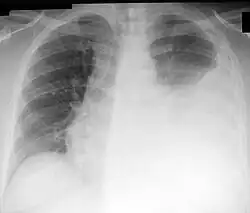

![]() Radiografía de tórax que muestra un derrame pleural izquierdo, susceptible de ser tratado con toracocentesis. | ||